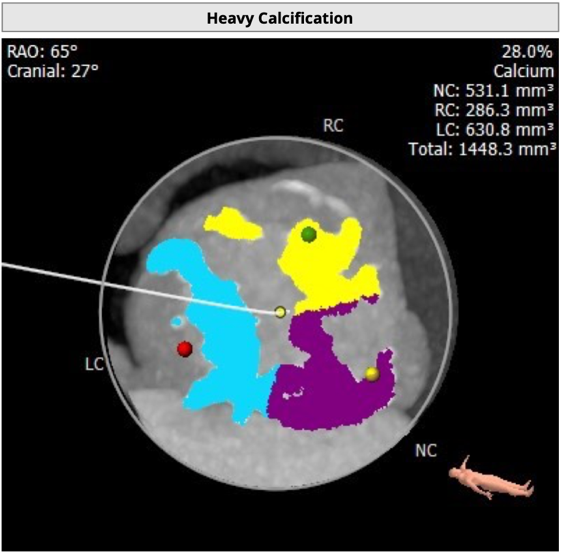

CT 数据显示该患者为Type1型二叶式主动脉瓣

瓣叶严重粘连增厚,瓣叶钙化明显,HU850:1448.3mm³。

左冠开口高度8.6mm,右冠开口高度15.0mm,左冠高度偏低,左冠瓣瓣尖钙化明显,根据瓦氏窦内径和瓣叶长度综合判断,左冠存在较高堵塞风险;左心室后壁增厚。